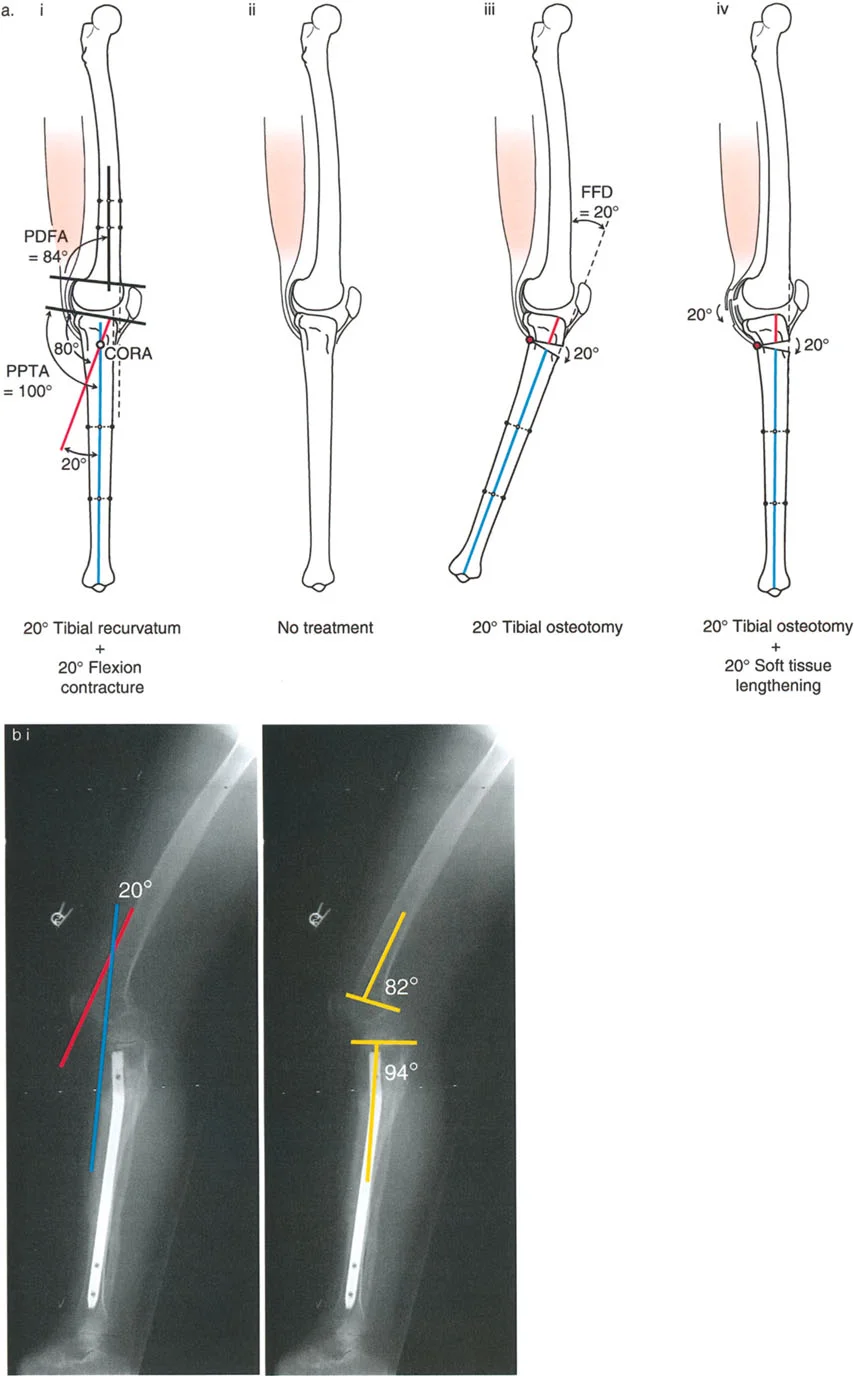

- على الرغم من أن الركبة الارتدادية هي فرط تمدد، إلا أنه في بعض الحالات، يمكن أن يترافق التشوه العظمي بتقلص في الأنسجة الرخوة يحد من انثناء الركبة. هذا التقلص يمكن أن "يخفي" أو "يعوض" جزئيًا فرط التمدد العظمي، مما يجعل الركبة تبدو في وضع تمدد طبيعي ظاهريًا.

- على سبيل المثال، إذا كان هناك ارتداد فخذي بمقدار 20 درجة مع تقلص انثناء 20 درجة، فقد تبدو الركبة في وضع تمدد كامل (0 درجة) ولكنها تعاني من فقدان في مدى الانثناء.

- تقييم مدى الحركة: يتم قياس مدى حركة الركبة، بما في ذلك أقصى تمدد وأقصى انثناء. يتم تحديد درجة فرط التمدد (HE - Hyperextension) أو درجة تقلص الانثناء الثابت (FFD - Fixed Flexion Deformity).

زوايا القياس الهامة:

- زاوية الانحناء البعيدة للفخذ (PDFA - Posterior Distal Femoral Angle): تقيس زاوية الجزء السفلي من عظم الفخذ. القيمة الطبيعية حوالي 84 درجة. الزيادة في هذه الزاوية (أكثر من 84 درجة) تشير إلى ارتداد فخذي.

- زاوية الانحناء القريبة للظنبوب (PPTA - Proximal Posterior Tibial Angle): تقيس زاوية الجزء العلوي من عظم الساق. القيمة الطبيعية حوالي 80 درجة. الزيادة في هذه الزاوية (أكثر من 80 درجة) تشير إلى ارتداد ظنبوبي.

- مركز دوران الزاوية (CORA - Center of Rotation of Angulation): يتم تحديد هذا النقطة على الأشعة السينية لتحديد مكان التشوه العظمي بدقة، وهو أمر بالغ الأهمية لتخطيط عملية قطع العظم.

- الركبة الارتدادية بسبب الارتداد الفخذي مع تقلص انثناء:

- إذا كان هناك ارتداد فخذي (PDFA > 84°) ولكن لا يوجد فرط تمدد سريري (HE = 0°)، فهذا يشير إلى وجود تقلص انثناء مصاحب يعوض التشوه العظمي.

- إذا كان فرط التمدد (HE) أقل من درجة الارتداد الفخذي، فهذا يعني وجود تقلص انثناء جزئي.

- الركبة الارتدادية بسبب الارتداد الظنبوبي مع تقلص انثناء:

- إذا كان هناك ارتداد ظنبوبي (PPTA > 80°) ولكن لا يوجد فرط تمدد سريري (HE = 0°)، فهذا يشير إلى وجود تقلص انثناء مصاحب.

- إذا كان فرط التمدد (HE) أقل من درجة الارتداد الظنبوبي، فهذا يعني وجود تقلص انثناء جزئي.

2. العلاج الجراحي: قطع العظم (Osteotomy)

الهدف من جراحة قطع العظم هو إعادة محاذاة العظام وتصحيح التشوه الزاوي في المستوى السهمي، لاستعادة وظيفة الركبة الطبيعية واستقرارها.

أ. قطع العظم الفخذي لتصحيح الارتداد الفخذي:

- متى يتم إجراؤها: عندما يكون التشوه الرئيسي في عظم الفخذ البعيد.

- الإجراء: يتم إجراء قطع للعظم (عادة قطع عظم انثناء) في الجزء البعيد من عظم الفخذ، عند مركز دوران الزاوية (CORA)، لإعادة محاذاة العظم.

- الهدف: تصحيح فرط تمدد الركبة واستعادة المحاذاة الطبيعية.

- مثال: لتصحيح ارتداد فخذي بمقدار 20 درجة، يتم إجراء قطع عظم انثناء فخذي بمقدار 20 درجة.